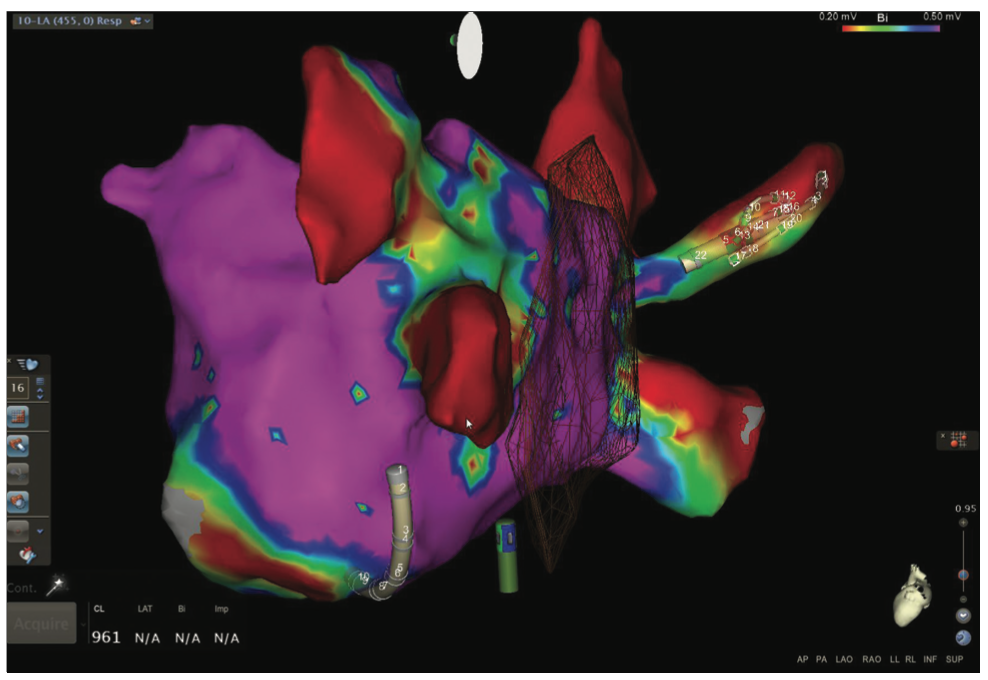

Video 11a and Figure 11b show the voltage map of the LA as well as the pliability of the Pentaray spline catheter to adapt its shape to vessels (a right middle vein) and the endocardium.